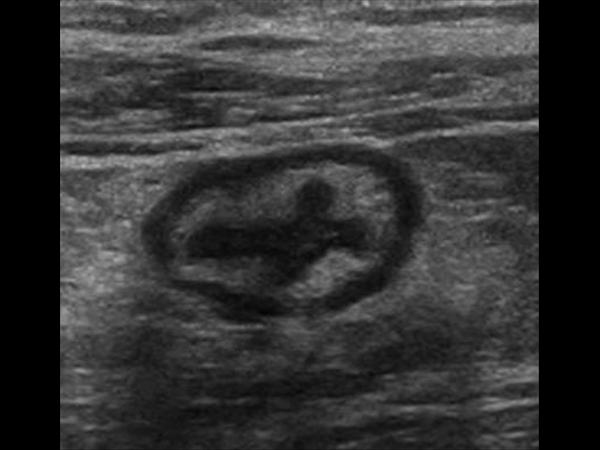

Viêm đại tràng

» Thông tin: Nam giới – 41 tuổi.

» Lâm sàng: Đau hạ vị.